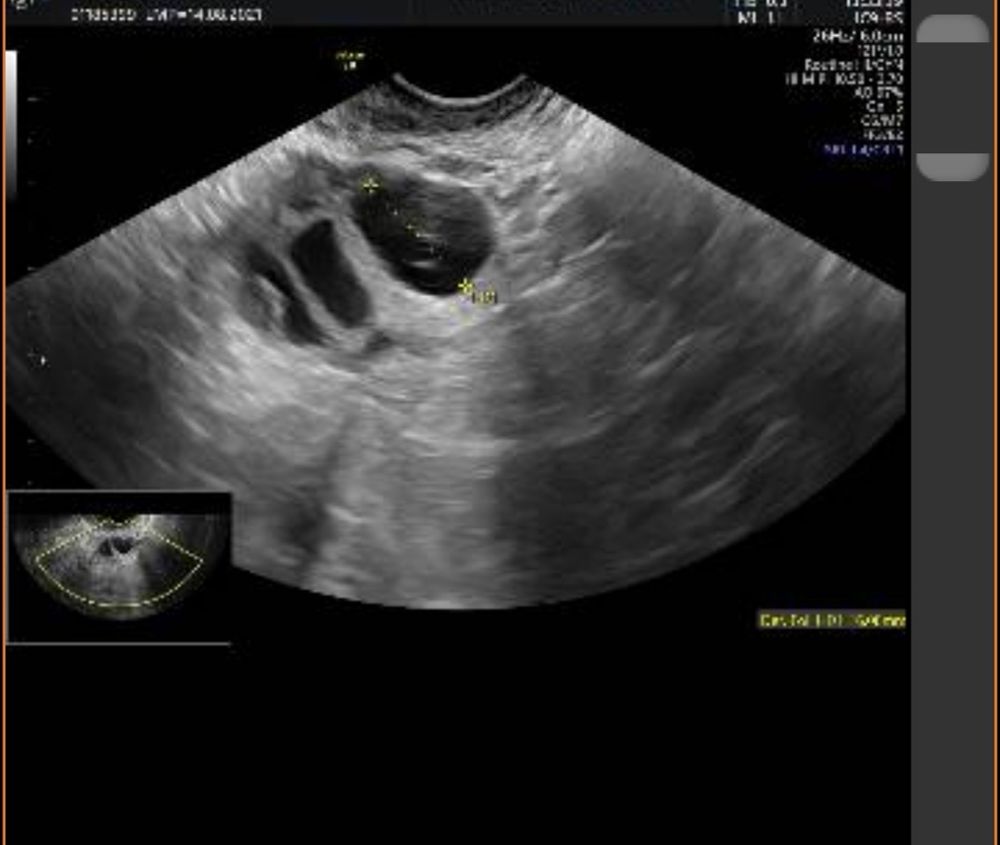

Жт или лютинизация фоликула?

Скоро два раза мама!!!))), ну у меня 1 дпо получается 20 мм. У меня лопаются 22-24 мм, на 4 дпо уже 26. Ну я так понимаю жт и лютинизированый фоликул трудно отличить. Надо сразу в день О смотреть. Просто на 1 дпо мне вообще левый врач смотрел.

Мила, у меня как-то в цикле стимуляции непонятки тоже были с УЗИ. В итоге пошла на экспертное УЗИ, дороговато конечно чем обычно, но хоть все по полочкам разложили. В итоге было 1 ЖТ, 1 лютеинизировавшийся фолликул и 1 в регресс ушел. По изображению лютеинизировавшийся фолликул и ЖТ очень похожи по мне, но врачи их как-то различают по кровотоку, содержимому и т.д.